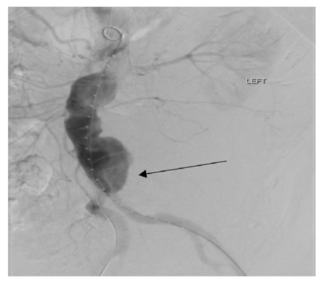

Ruptured abdominal aortic aneurysms (rAAA) represent the 13th leading cause of mortality in the United States.

The authors developed and evaluated a novel hybrid approach to retrograde SMA revascularization via jejunal arterial access that requires a mini-laparotomy.